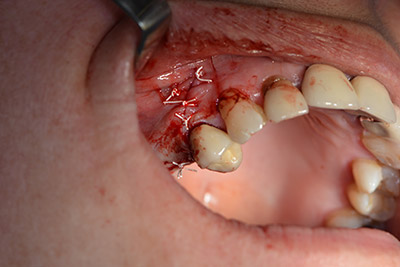

The following holes were drilled at a reduced speed of 300 rpm. The Implantmed demonstrated its true capability at this stage. The surgical protocol can be preset – the various positions can be selected simply by pressing the “P” position of the foot control (Fig. 10 to 11).

Inclined drilling

Image 10: Inclined drilling to dorso-cranial at 300 rpm.